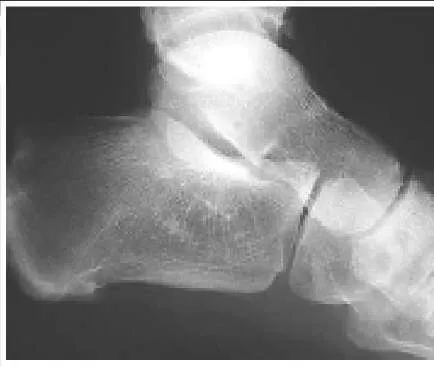

A 15-year-old boy presents with a 2-year history of pain in the foot associated with a sense stiffness and of giving way of the ankle. Upon examination, pain in the sinus tarsi, slightly decreased subtalar motion, and normal ankle motion with no apparent instability are noted. A lateral foot radiograph is presented. The next radiograph to obtain is:

Correct Answer: Axial view of the hindfoot

This child presents with symptoms suggestive of a tarsal coalition. There is stiffness, and symptoms of ankle discomfort or instability. On the lateral radiograph, there is consolidation of trabeculation under the posterior facet in the shape of a â C â , a typical finding of a middle facet coalition, which should be investigated further with an axial view of the subtalar joint (Harris).